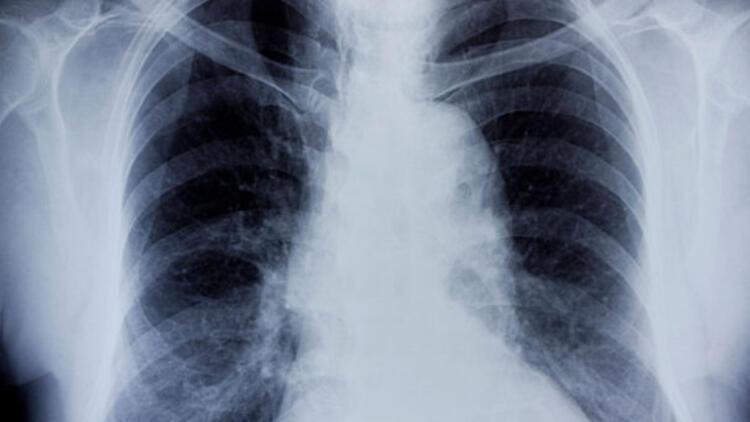

Bebeklerde Bronşit Neden Olur

Bebeklerde Bronşit Neden Olur.

cocuklarda bronsit belirtileri ve tedavisi kadinlar kulubu